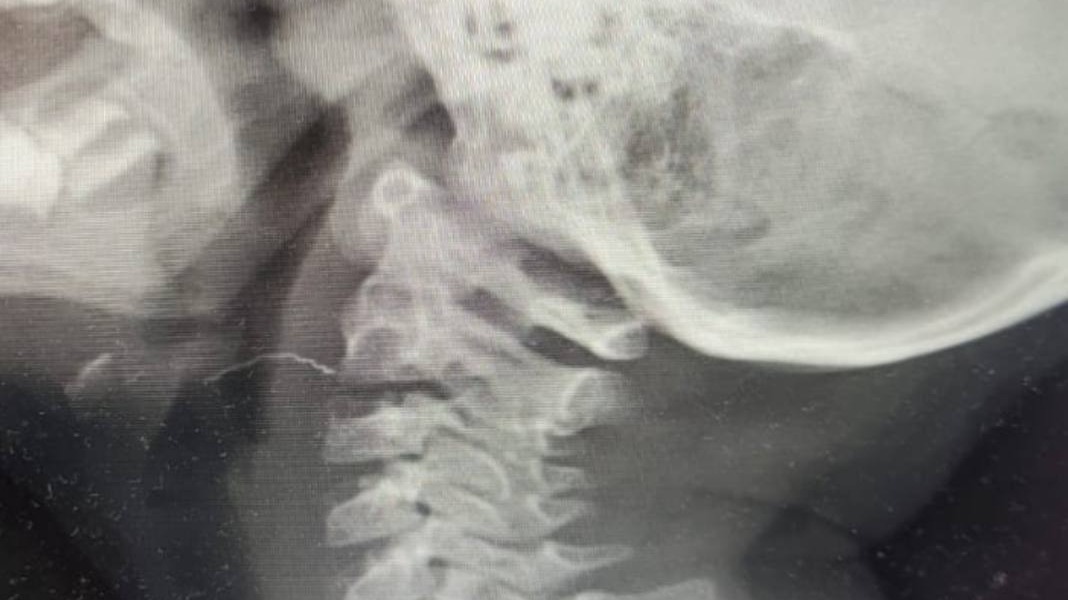

Фото: Пресс-служба Министерства здравоохранения Московской области

Столичные врачи достали из горла двухлетней девочки проволоку, с которой она проходила больше недели. Об этом в четверг, 18 июля, сообщили в пресс-службы Минздрава Московской области.

Жительница Подмосковья привела в больницу двухлетнюю дочь, у которой больше недели болело горло. Во время осмотра врачи обнаружили в горле ребенка двухсантиметровую проволоку. Выяснилось, что малышка случайно проглотила ее во время завтрака.

Девочку экстренно госпитализировали в столичное отделение оториноларингологии МОНИКИ и провели операцию.

— Если бы проволока находилась в организме дольше, то, учитывая совсем юный возраст пациентки, это могло привести к различным гнойным осложнениям и лечение было бы совсем другим, — рассказал врач Виктор Егоров.

Пациентку уже выписали из больницы, ее жизни ничего не угрожает.